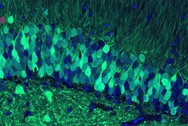

Engram

What a Memory Looks Like

Your brain has the capacity to store a lifetime of memories, covering everything from the name of your first pet to your latest computer password. But what does a memory actually look like? Read more...